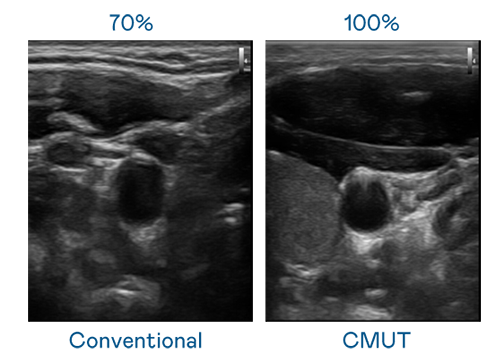

CMUT 技术是一种用电容式微机电元件来产生超音波讯号的技术。与传统 PZT 压电式技术相比,CMUT 频宽增加 30%,更宽频的超音波讯号让影像解析度大幅提升,是实现高影像品质医疗超音波扫描、促进精准医疗发展的关键技术。

超音波影像的解析度高低,首先取决于探头能发出的讯号频宽。利来w66 CMUT 可提供高清晰的超音波讯号,提供高频宽、高灵敏度、影像纹理细节更高的超音波影像,协助医护人员缩短影像判读时间及利用精准的医疗影像进行诊断。